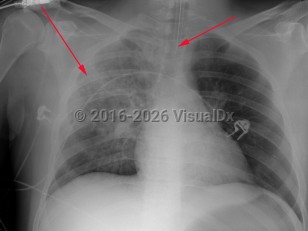

Staphylococcus aureus pneumonia - Pulmonary

Staphylococcus aureus in responsible for about 1%-10% of community-acquired pneumonias and 20–30% of hospital-acquired pneumonias. Staphylococcus aureus pneumonia may result from air-borne contamination or aspiration or hematogenous seeding of the lungs from bacteremia or right-sided endocarditis. There may be a history of recent viral or influenzal illness. The clinical manifestations of staphylococcal pneumonia are similar to other causes of pneumonia except for a tendency to cause necrotizing infection with tissue destruction and cavitation. The patient will present with an abrupt onset of fever, tachypnea, pleuritic chest pain, and a productive cough with purulent sputum, which can be blood-tinged. Staphylococcus aureus is also one of the most common causes of empyema. In cases with accompanying endocarditis, stigmata-like subungual hemorrhages, murmur of aortic, tricuspid or mitral regurgitation, palmar Janeway lesions, and digital Osler nodes may be found.